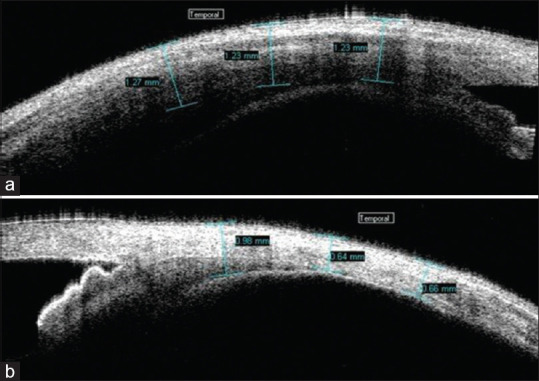

Purpose: The purpose of this study was to evaluate the role of anterior segment optical coherence tomography (ASOCT) in the diagnosis and management of anterior scleritis.

Patients and methods: In this retrospective study, we examined 58 eyes of 44 patients with anterior scleritis. The unaffected eye served as a control. In bilateral cases, the less affected eye was taken as the control. ASOCT image over the inflamed area and over the corresponding same area in the control eye was taken. The images were analysed for the presence or absence of hyporeflective areas, and the mean total scleral thickness (MTST) was measured. Both the images were then compared.

Results: The mean age of our cohort was 51 ± 14.57 years. There were 14 males and 30 females. 68.18% (n = 30) were unilateral cases. The mean duration of anterior scleritis was 55.3 months, with 50% (n = 22) of patients having diffuse anterior scleritis. The majority of patients were treated with oral steroids (97.7%, n = 43) with or without the combination of immunosuppressant and biologics. The MTST during active disease (922.17 μm ± 252.03 μm) was statistically higher than the control group (798.05 μm ± 150.61 μm) (P = 0.005). The MTST in unilateral cases during active disease was 929.88 μm, which was significantly higher than in the control eyes (801.65 μm) (P = 0.02). There were 31 recurrent cases, of which 41.9% (n = 13) showed scleral thinning, and the mean scleral thinning in recurrent cases after treatment was 86.71 μm.

Conclusion: ASOCT serves as a useful qualitative and quantitative tool for monitoring of patients with anterior scleritis under treatment.